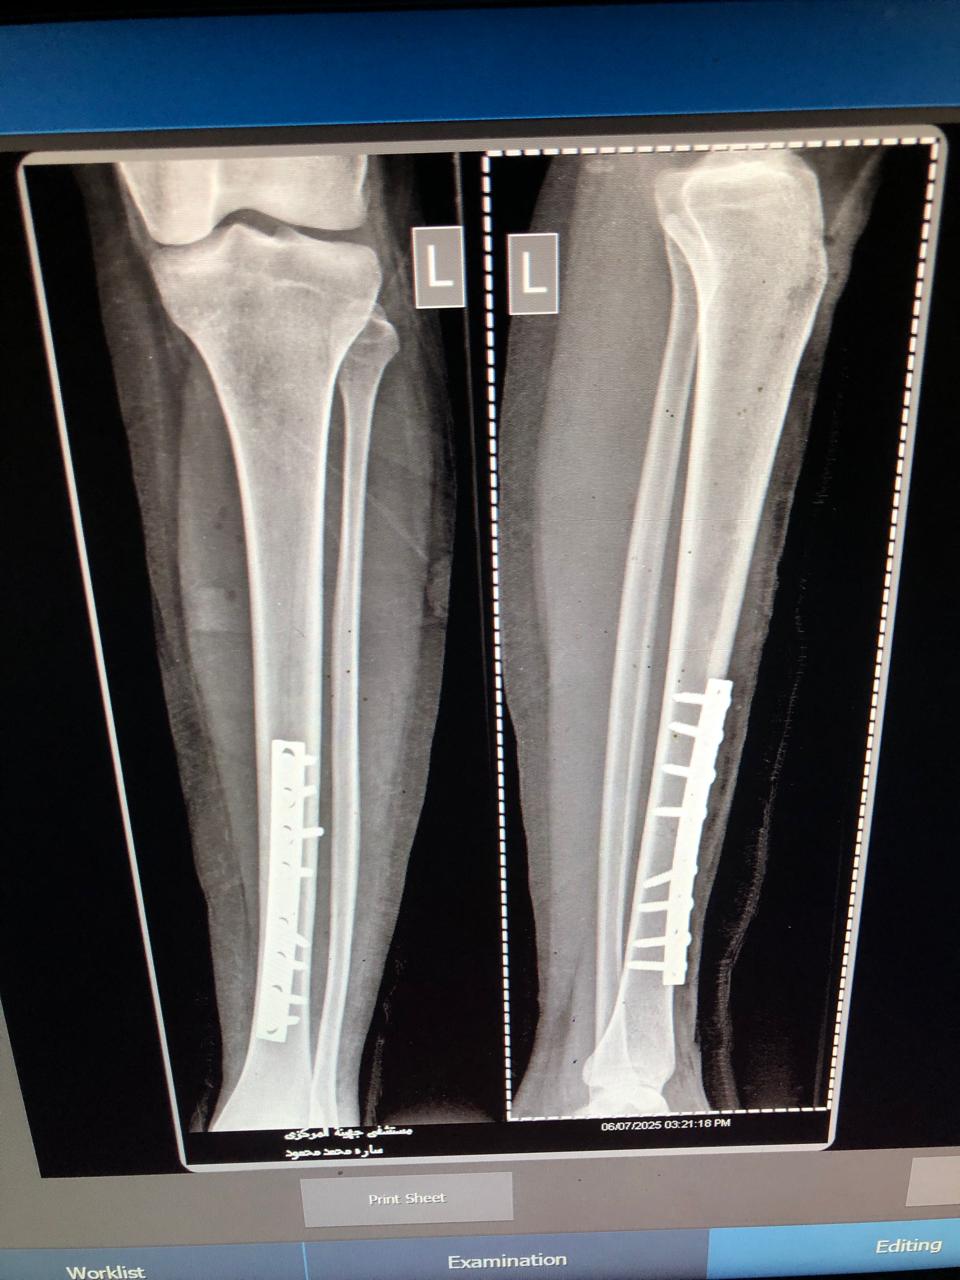

وتم إجراء 3 عمليات دقيقة، شملت تركيب شرائح ومسامير ومسامير نخاعية لثلاث حالات من الطليحات ونزة الدقيشة، بينما تواصل باقي الحالات تلقي العلاج اللازم بالمستشفى.